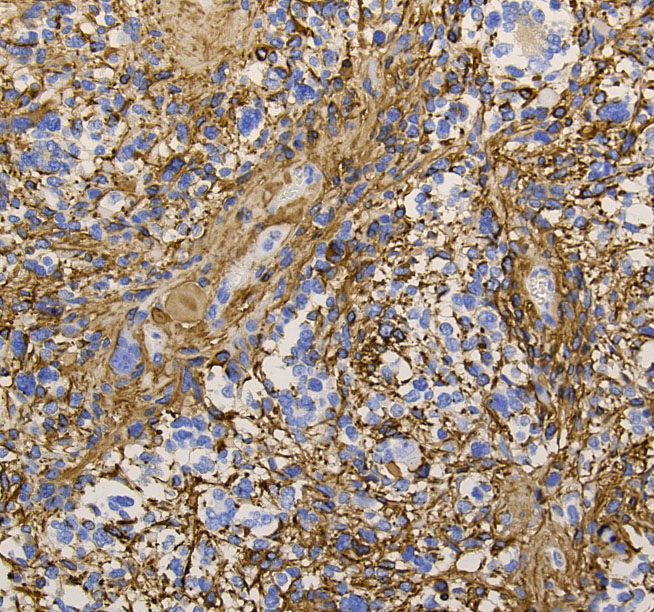

病理組織像を見たら次に遺伝子診断をして確定病理診断とします

glioblastomahe2

これは普通の病理組織診断です。これだけで膠芽腫という診断はつきます,

2022年時点での病理学での定義と臨床

• 組織学的には,びまん性の星細胞系グリオーマであり,血管内皮増生と壊死が特徴です

• IDHとH3遺伝子には変異がありません 野生型 wild typeといいます

• 特異的な遺伝子異常として,TERT promoter mutation, EGFR gene amplification and/or a +7/–10 cytogenetic signatureがみられます

• 組織診断で低悪性度びまん性星細胞腫でも,IDH wild typeでかつ,TERT promoter mutation, EGFR gene amplification, +7/–10 copy number changes のどれか一つがあれば,膠芽腫グレード4と診断します

下の病理写真は,ある患者さんから私に送られたものです。20代で前頭葉の膠芽腫になってから21年経って生存しておられるということです。2度の開頭術と放射線治療と化学療法(複数回)を受けておられます。患者さんに病理診断が間違っているのではないかと返事をしたら,下にある画像を送ってくださいました。病理診断は,一見したところは多形膠芽腫 グリブラに間違いありませんでした。でも,ーーー

(下の画像は患者さんの許可を得て掲載させていただきました)

bizarre! 異様な細胞が混在しています。核多型が目立ち,多核巨細胞も混じる典型的な膠芽腫の像です。下の左の画像は血管内皮の肥厚 endovascular proliferationがあり,下の右のKi-67染色では核濃染像が多く核分裂能が高いことを示します。しかし,——

左のGFAP染色では一部の細胞が染色されません,右のHE染色では豊富な血管増殖の間に空砲 perinuclear halo を有した細胞増殖が見られます。さらに,–

腫瘍の部分像として明らかに乏突起膠腫が混在しています。また,どの部分をみても壊死 necrosisがありませんでした。

従って,当時の診断では,この腫瘍の形態病理診断は,退形成性乏突起星細胞腫 anaplastic oligoastrocytoma WHO grade III となります。2018年時点では,もしiDH変異があったと仮定すると,secondary glioblastoma (IDH-mutated glioblastoma)とされるかもしれません。